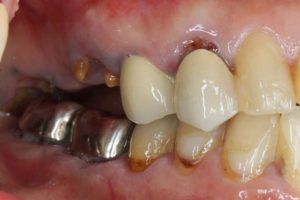

どのように変わったか、下の写真をご覧ください。

治療お疲れ様でした。たくさん銀歯が入っていたのですが、最後には真っ白になりましたね。銀歯をやり直す材料にはセラミックとプラスティックがあるのですが、基本的にできるだけプラスティックで治すようにしています。この患者さんも、可能な限りプラスティックで治し、どうしても無理なところだけセラミックにしました。そのため歯を削る量が少ないことに加え、費用もかなり抑えることができます。たくさん治しましたが、全部セラミックで治さなければならないとなっていたら、もっともっと時間も費用もかかっていたかもしれません。当院では、初診時に治療方針や期間や費用などを1時間ほどかけて詳しく説明していますので、患者さんには治療内容について十分納得していただいていると考えています。「親身になって治療してくれる」とおっしゃっていただいたことは、そういったところを評価して頂いたのではいかと思っております。